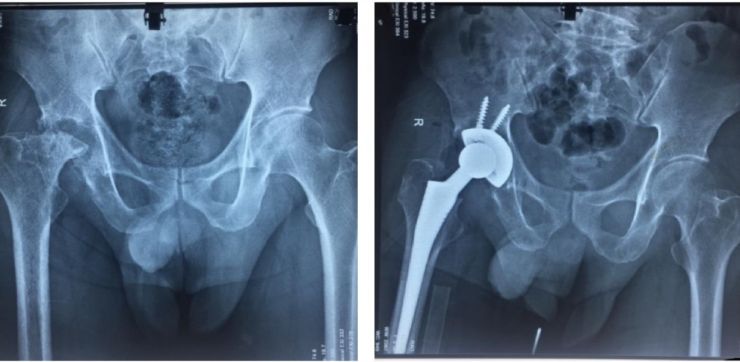

Một người dân 53 tuổi, cư ngụ tại quận Gò Vấp đến bệnh viện quận Gò Vấp khám vì tình trạng đau nhức khớp háng bên phải gây hạn chế vận động, di chuyển kéo dài khoảng 1 năm nay. Sau khi được thăm khám và chụp X-quang kiểm tra, bác sĩ phát hiện người bệnh bị hoại tử chỏm xương đùi phải, có chỉ định thay khớp háng nhân tạo.

Các bác sĩ chuyên khoa Chấn thương Chỉnh hình của Bệnh viện Nhân dân Gia Định cùng với các y, bác sĩ của Bệnh viện quận Gò Vấp phẫu thuật thay khớp háng